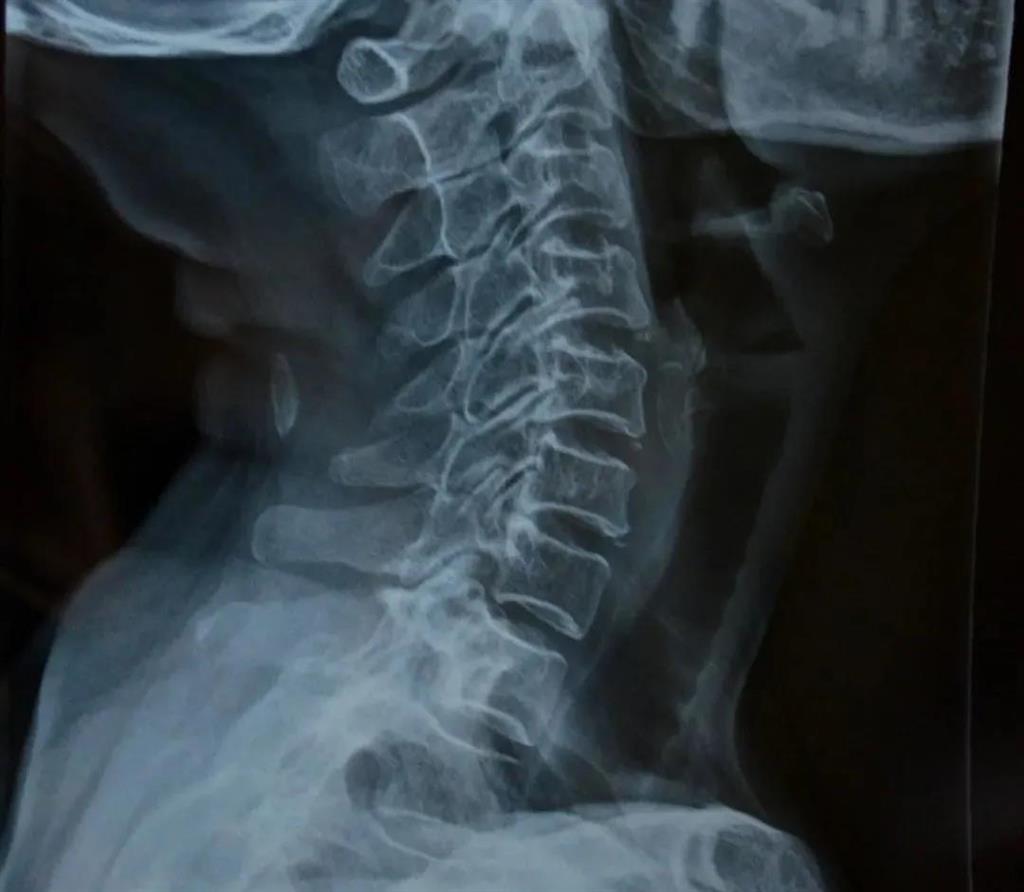

X光片檢查

——圖源網(wǎng)絡(luò)

可得信息:

(1)判斷頸椎的大體形態(tài)、曲度、穩(wěn)定性;

(2)判斷骨頭結(jié)構(gòu)是否出現(xiàn)破壞的情況;

(3)是否出現(xiàn)骨質(zhì)增生或先天畸形的情況。